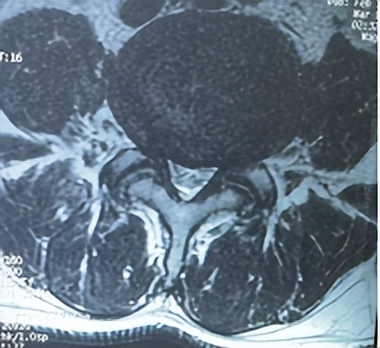

腰3/4、腰4/5两个节段椎管狭窄

66岁男性患者,腰3/4、腰4/5两个节段椎管狭窄,左下肢放射性疼痛、麻木2个月余,间歇性跛行,保守治疗无效。其爱人9年前患腰椎间盘突出症,副主任医师石立刚利用微创椎间孔镜治疗后,至今效果满意。此次慕名前来。